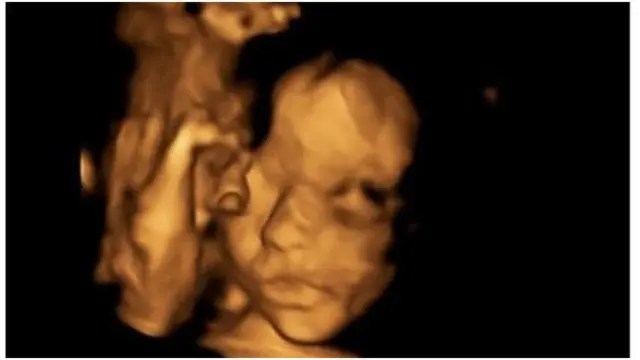

Waxaa qalliin lagu guuleystay oo lafdhabarta ah lagu sameeyay ilma yar oo aanan wali dhalan.

Qaliin ilmagaleenka ah oo soconayay afar saacadood ayaa uur-jiifka banaanka loo soo saaray, iyada oo dhaqaatiirta qaliinka wadayna ay ku toosiyeen qalooc ku jiray qeybta hoose ee lafdhabarta.

Qaliinka lagu sameeyay ilmaha caloosha ku jiray ayaa la rumeysan yahay inuu guuleystay waxa uuna dhalan doona bishi April ee soo socota.

Qaliinka lagu sameeyay toddobaadkii 24-aad ee uur ku jirta ayaa waxaa qeyb ka ahaa furitaanka ilmagaleenka iyo in dhinac kale loo dhigo uur-jiifka si loo toosiyo qalooca, iyo sidoo kale dib u habeynta lafdhabarta.